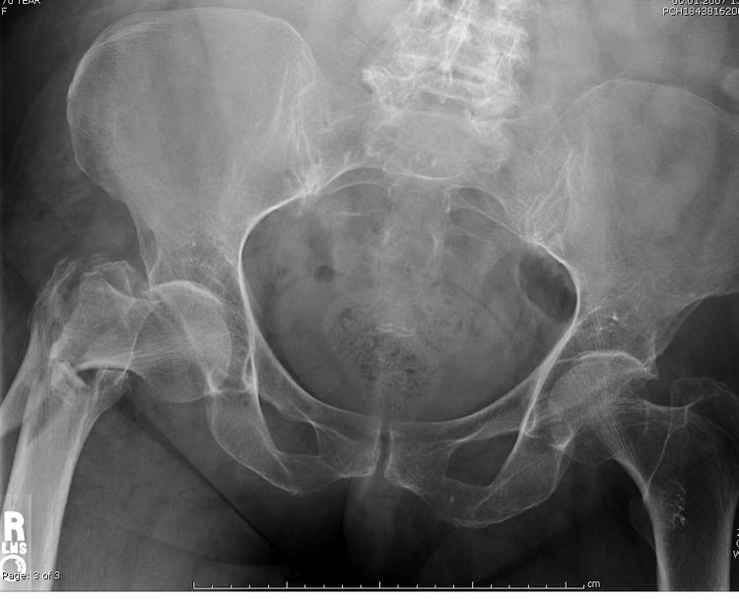

Re: Чрезвертельный перелом бедра

Здесь 83 года, травма в результате падения